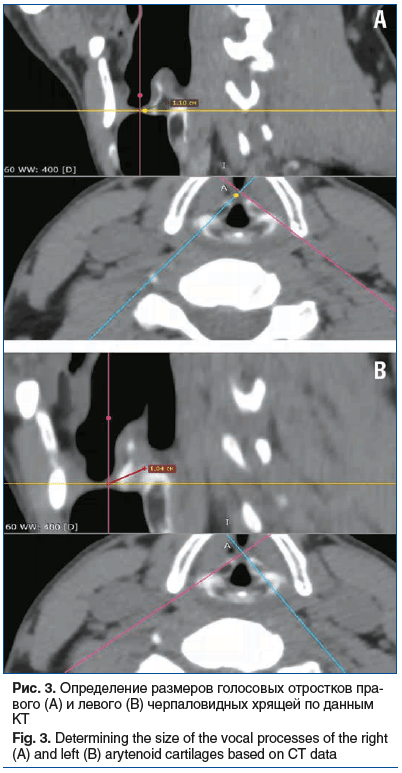

Учитывая длительность сохранения гранулемы на задней трети истинной голосовой связки (2,5 года), отсутствие положительной динамики от назначенной оториноларингологической и гастроэнтерологической терапии, мы предположили, что есть отягощающий фактор (в нашем случае это голосовой отросток правого черпаловидного хряща), который при фонации «травмирует» противоположный левый голосовой отросток, препятствуя купированию воспалительного процесса. При обследовании пациента было выявлено, что длина голосового отростка правого черпаловидного хряща составляет 1,10 см, в то время как слева — 1,04 см (рис. 3). Мы предполагаем, что более длинный правый голосовой отросток во время фонации оказывает повышенное механическое воздействие на область задней трети левой голосовой складки, где расположена КГ. Постоянная травматизация этой зоны может препятствовать полноценному заживлению и способствовать переходу хронического воспалительного процесса, ограниченного слизистой оболочкой, на хрящевые структуры гортани (голосовой отросток черпаловидного хряща), что обусловливает хронизацию процесса.